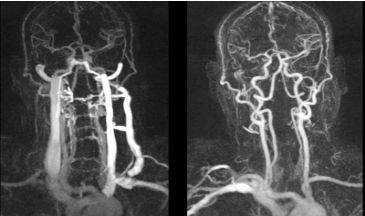

КТ снимки сосудов шеи

КТ-ангиография сосудов шеи с контрастом - золотой стандарт диагностики, но чтобы получить максимальную пользу от исследования, необходима слаженная работа профессионалов. Расшифровкой результатов занимается рентгенолог. В центре “Магнит” в Санкт-Петербурге КТА - одна из востребованных процедур, а наши врачи ответят на любые вопросы. В сложных случаях оценка томограмм проводится коллегиально. Представляем Вашему вниманию несколько томограмм, где четко видны патологические изменения:

КТ-ангиограмма кровеносных сосудов в области шеи. Позвоночная артерия находится между вертикальными линиями. Стрелка указывает на позвоночник

3D-изображения компьютерной мультиспиральной томографии Виллизиева круга. Его контуры можно увидеть на томограмме в центре, шея внизу, основные артерии белого цвета.

Коронарное изображение МСКТ демонстрирует саккулярный затек контраста (толстая стрелка) из правой внутренней сонной артерии (псевдоаневризма). Левая сонная артерия (тонкая стрелка) не повреждена.